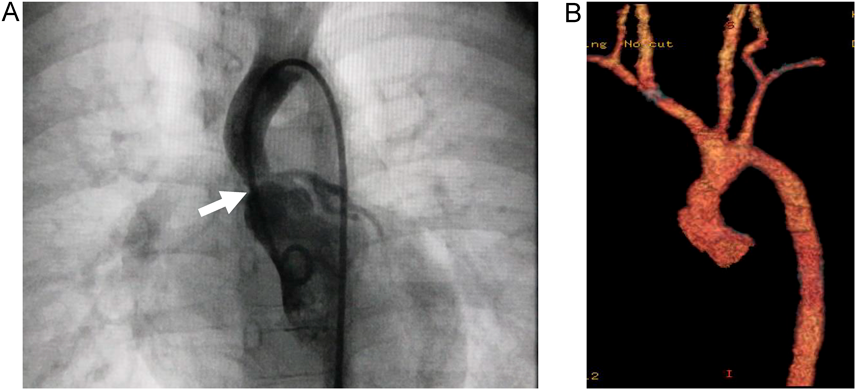

Fig. 2 Radiographic images

(A) Preoperative left ventriculography. The ascending aorta is narrow above the Valsalva sinus (arrow). (B) Postoperative enhanced computed tomography. The ascending aorta appears less obstructed morphologically.

This patient was first diagnosed with a heart murmur at the age of 6 months. Echocardiography showed mild SVAS and mild peripheral pulmonary stenosis. She was suspected of Williams syndrome on the basis of intellectual disability, characteristic appearance, and concomitant cardiac defects at the age of 3 years. The chromosomal analysis confirmed the disorder with 7q11.23 microdeletion by fluorescence in situ hybridization. Pressure gradient of 50 mmHg was observed across SVAS on continuous-wave Doppler (CW) at the age of 4 years. LV end-diastolic septal thickness, LV end-diastolic posterior wall thickness, and LV end-diastolic diameter were 4.6 mm with z score −1.15*, 5.5 mm with z-score 1.06*, and 25.5 mm with z-score −3.12*, respectively, indicating no LV wall hypertrophy or enlargement (*according to a web site (https://zscore.chboston.org), based on body surface area with 0.57 m2; for the LV end-diastolic posterior wall, the LV end-diastolic free wall thickness on the site was applied). LV systolic function was normal. LV diastolic function, including the early to late diastolic mitral flow velocity ratio, was not evaluated. ECG did not meet the criteria for electrocardiographic LV hypertrophy; RV5=1.7 mV, RV6=1.4 mV, SV1+RV5=3.5 mV, and SV1+RV6=3.2 mV.2) NU was observed in V5 and V6 leads (Fig. 1A). Pressure study on cardiac catheterization revealed pressure difference of 50 mmHg between the LV and the ascending aorta. The ascending aorta was narrow above the Valsalva sinus on LV-graphy (Fig. 2A). After repair of SVAS (Fig. 2B), pressure gradient estimated by CW improved to 25 mmHg. At 5 months after surgery, NU in V5 and V6 leads disappeared (Fig. 1B).